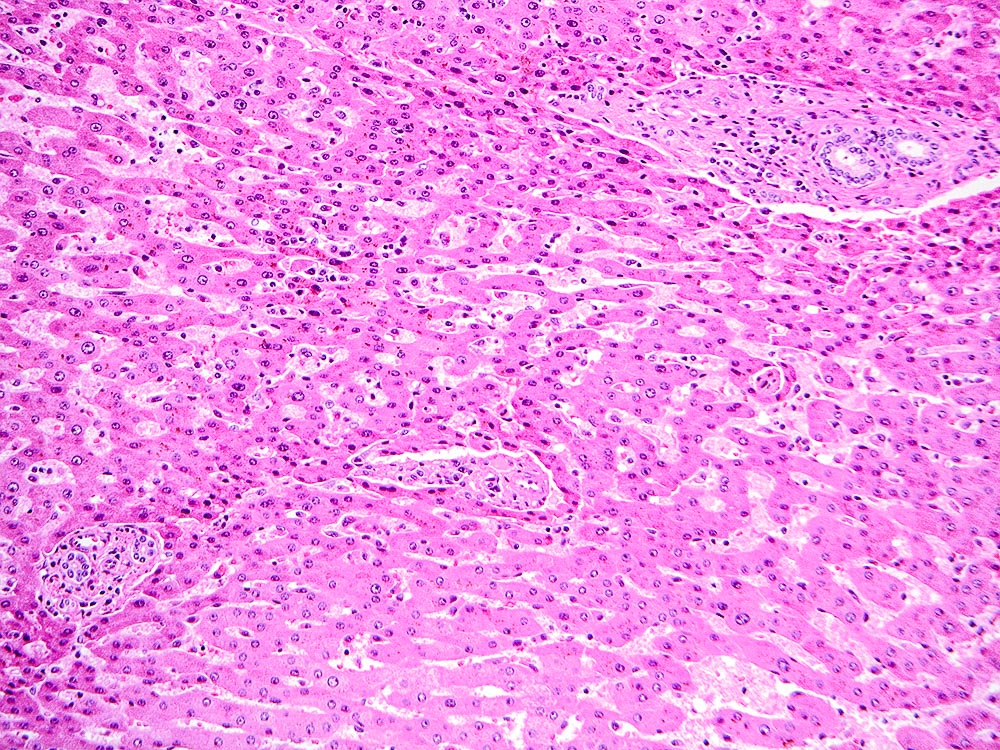

The explant showed a nodular liver with areas of sinusoidal dilatation, and occasional incomplete septae, but no evidence of cirrhosis. Rare florid ducts of PBC are present but there is mild ductopenia that came down to approximately just 20% of the terminal bile ducts; the larger bile ducts appear normal as are most of the small/terminal bile ducts. Several small portal tracts however have increased portal and occasionally periportal fibrosis and no visible portal veins. The larger portal tracts often have small portal veins when compared with the corresponding hepatic artery or bile duct, with thickening of the veins walls (obliterative portal venopathy). Reticulin stain demonstrates nodularity not bordered by fibrous septae, the edge of the nodules having compressed reticulin fibers (NRH). Sections from the hilum demonstrate major but non-occlusive portal vein thrombus.

Non-cirrhotic portal hypertension from a combination of nodular regenerative hyperplasia (NRH), portal vein thrombosis, and obliterative portal venopathy (OPV) in a patient transplanted for Primary Biliary Cirrhosis